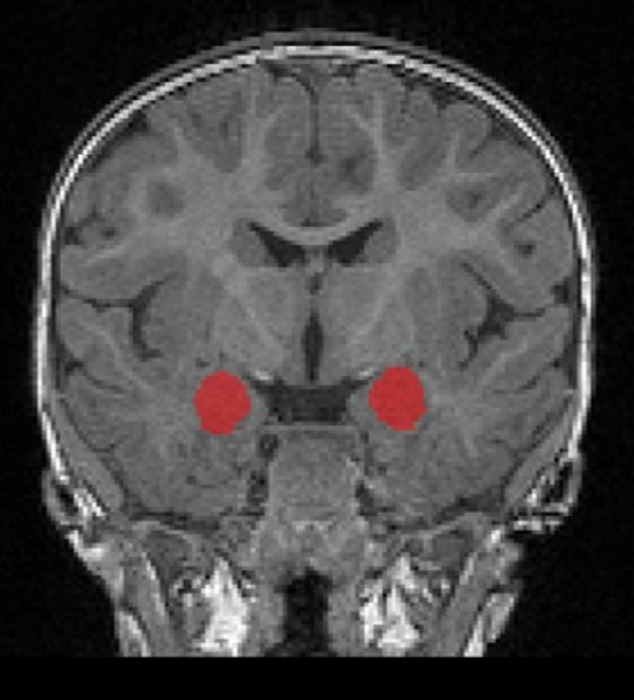

image: The amygdala (in red) grows too rapidly in babies (6-12 months) who later develop autism as toddlers. view more

CHAPEL HILL, NC – The amygdala is a small structure deep in the brain important for interpreting the social and emotional meaning of sensory input – from recognizing emotion in faces to interpreting fearful images that inform us about potential dangers in our surroundings. Historically the amygdala has been thought to play a prominent role in the difficulties with social behavior that are central to autism.

Researchers have long known the amygdala is abnormally large in school-age children with autism, but it was unknown precisely when that enlargement occurs. Now, for the first time, researchers from the Infant Brain Imaging Study (IBIS) Network, used magnetic resonance imaging (MRI) to demonstrate that the amygdala grows too rapidly in infancy. Overgrowth begins between six and 12 months of age, prior to the age when the hallmark behaviors of autism fully emerge, enabling the earliest diagnosis of this condition. Increased growth of the amygdala in infants who were later diagnosed with autism differed markedly from brain-growth patterns in babies with another neurodevelopmental disorder, fragile X syndrome, where no differences in amygdala growth were observed.

Published in the American Journal of Psychiatry, the official journal of the American Psychiatric Association, this research demonstrated that infants with fragile X syndrome already exhibit cognitive delays at six months of age, whereas infants who will later be diagnosed with autism do not show any deficits in cognitive ability at six months of age, but have a gradual decline in cognitive ability between six and 24 months of age, the age when they were diagnosed with Autism Spectrum Disorder in this study. Babies who go on to develop autism show no difference in the size of their amygdala at six months. However, their amygdala begins growing faster than other babies (including those with fragile X syndrome and those who do not develop autism), between six and 12 months of age, and is significantly enlarged by 12 months. This amygdala enlargement continues through 24 months, an age when behaviors are often sufficiently evident to warrant a diagnosis of autism.

“We also found that the rate of amygdala overgrowth in the first year is linked to the child’s social deficits at age two,” said first author Mark Shen, PhD, Assistant Professor of Psychiatry and Neuroscience at UNC Chapel Hill and faculty of the Carolina Institute for Developmental Disabilities (CIDD). “The faster the amygdala grew in infancy, the more social difficulties the child showed when diagnosed with autism a year later.”